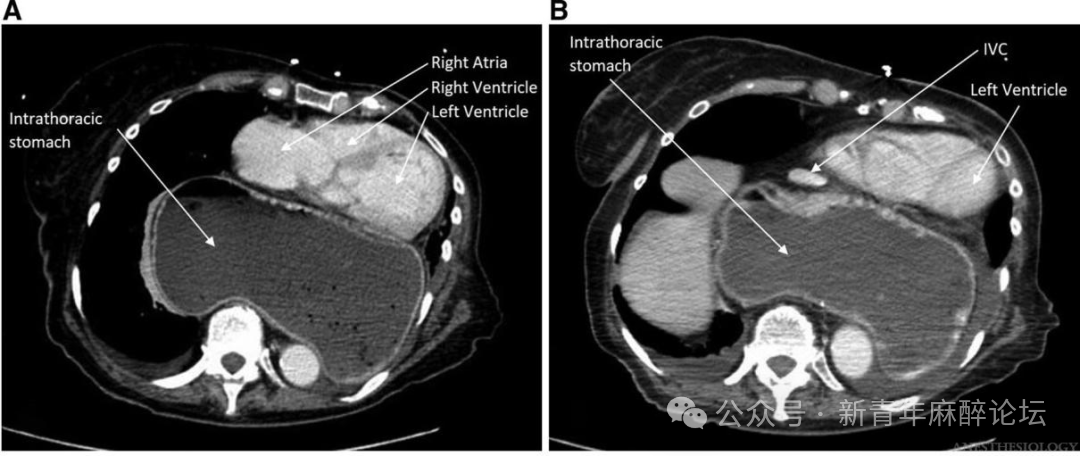

图1A:胸部CT影像显示大体积胸内胃占据胸腔空间,对心脏结构(右心房、右心室及左心室)形成显著的占位效应,致其受压、移位。

图1B:胃囊同时压迫下腔静脉,使其管腔明显狭窄。